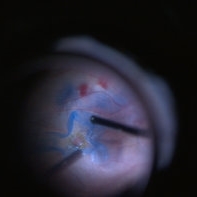

Macular Hole With Folded ILM

This is a freeze frame taken from a large vitrectomy for macular hole where I folded the ILM in a cone around the hole before fluid air exchange.